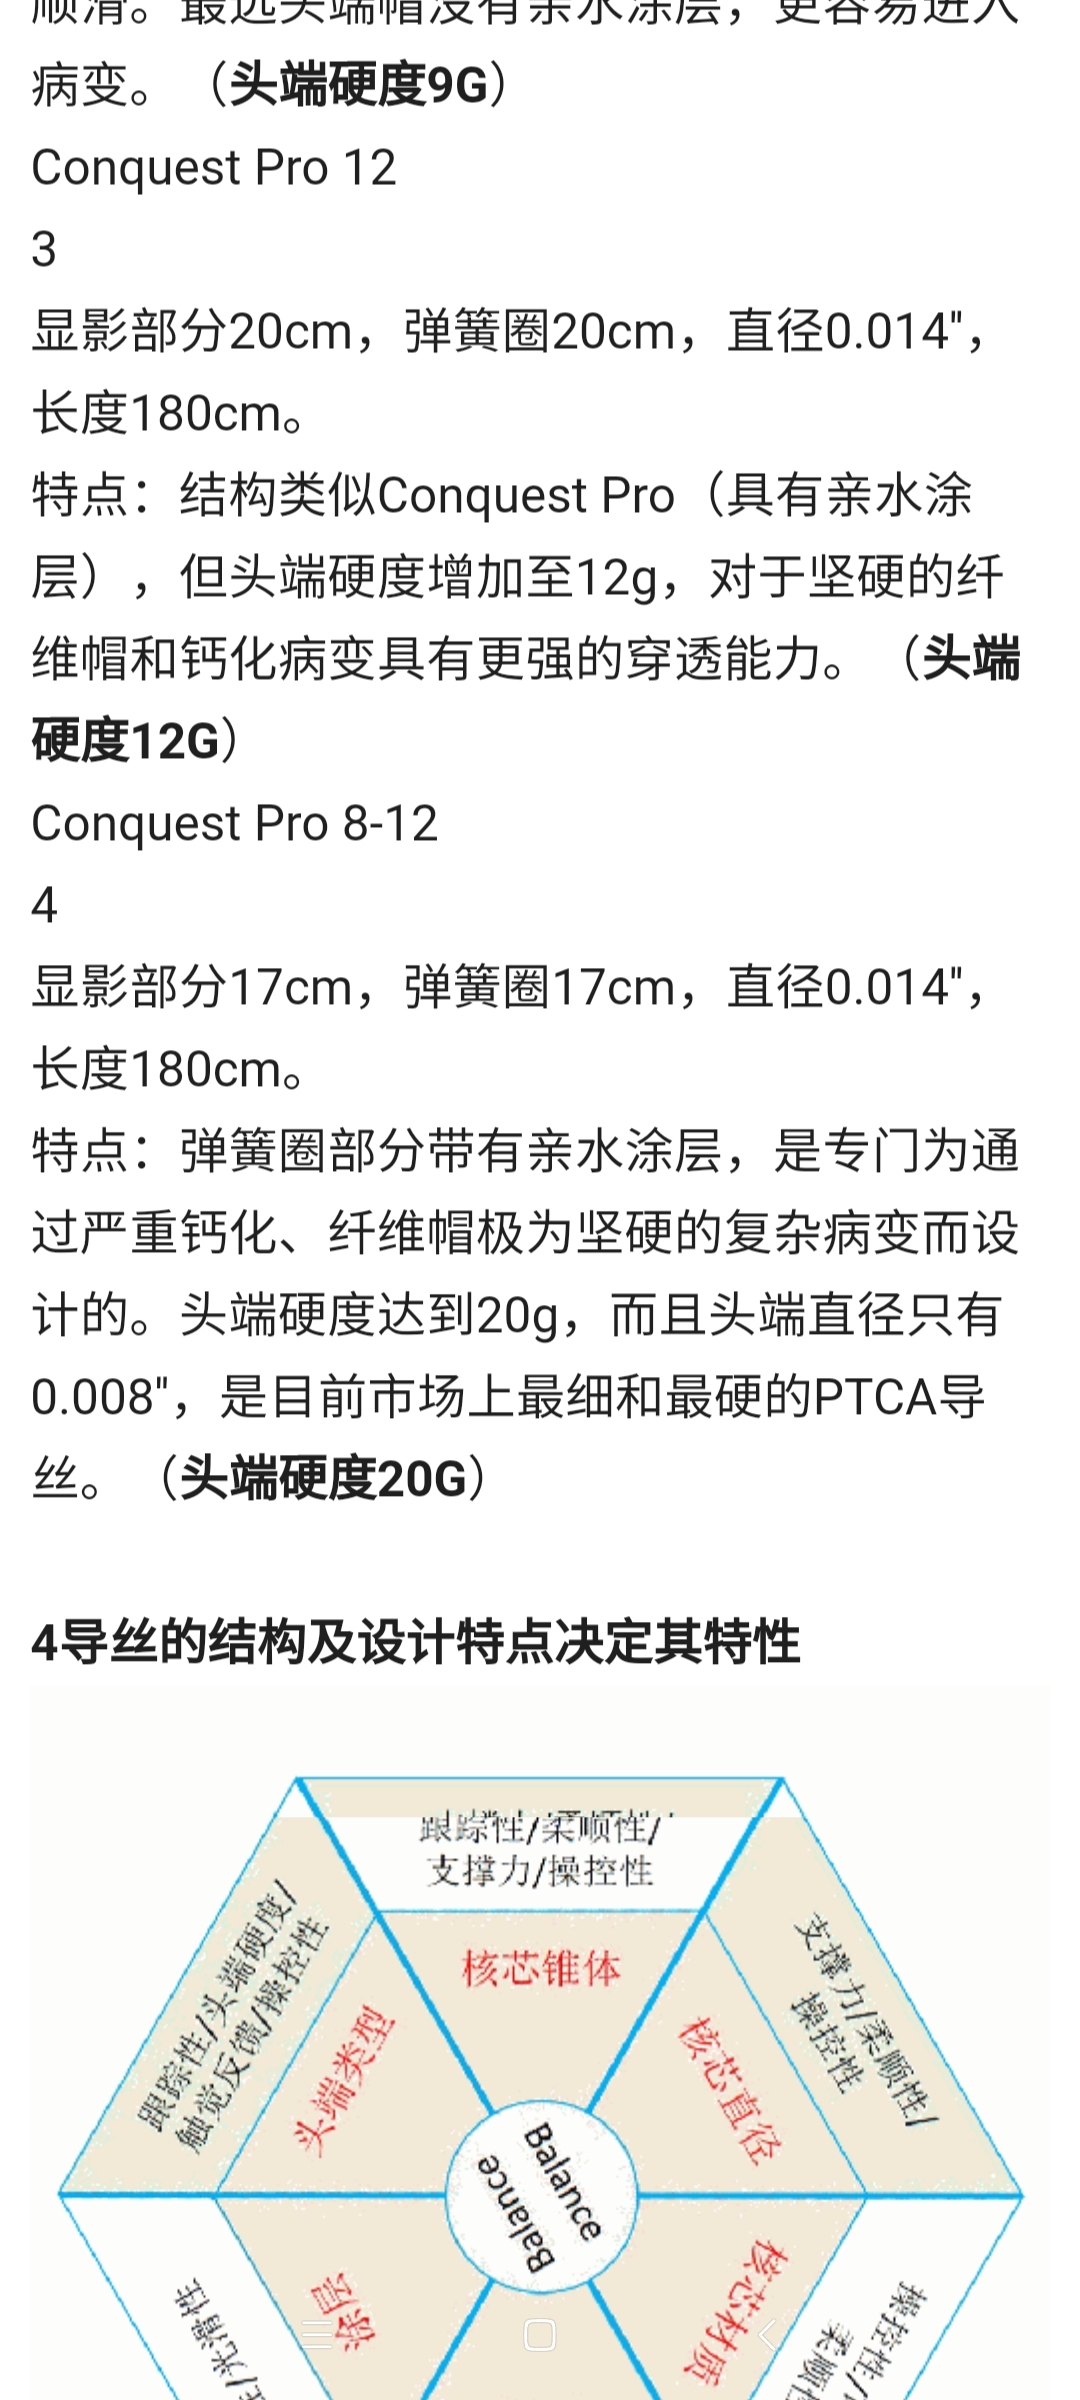

备好心心念的Conquest Pro 8-20,准备开干